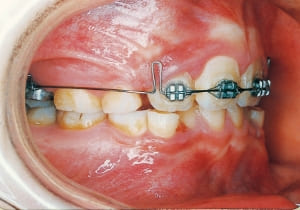

17 At start of full bracket treatment 5-18-’92

18 Treatment progress 4-11-’94

In the maxilla, insufficient space for canine eruption was inevitable, necessitating extraction as part of the treatment plan. The maxillary first premolars on both sides were extracted during routine observation to create space for canine eruption (14). Eventually, the canines erupted and settled into relatively favorable positions (15,19,20). In the mandibular dentition, crowding was also present, leading to extraction of the mandibular first premolars on both sides. Treatment with full bracket was then initiated (17).